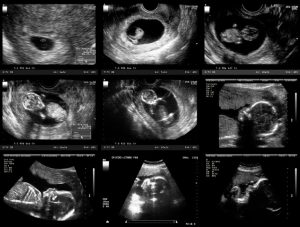

سونوگرافی در تشخیص ناباروری

سونوگرافی یکی از اصلیترین ابزارهای تشخیص ناباروری است.

سونوگرافی ترانسواژینال برای بررسی رحم و تخمدانها

ارزیابی ذخیره تخمدان (تعداد فولیکولها)

پایش رشد فولیکول و زمان تخمکگذاری